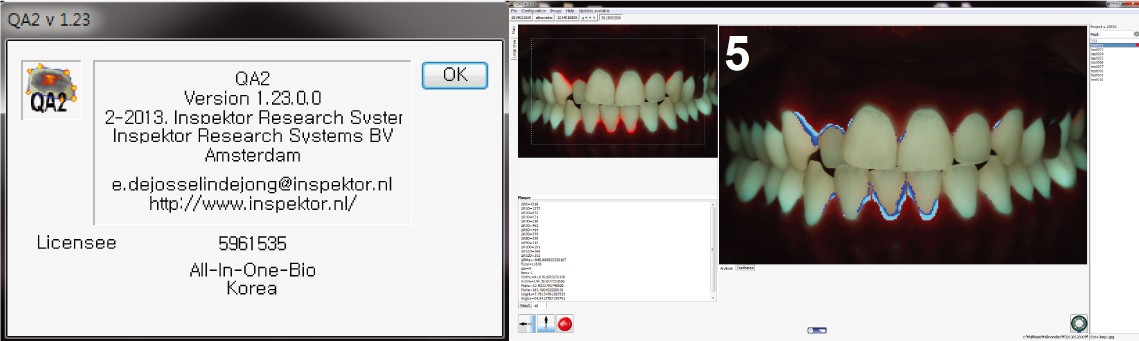

QLF-D분석프로그램(QA2)

C3프로그램을 통해 저장된 이미지를 분석하여 구강 내 상태의 세균분포정도를 정량적 정성적으로 분석하는 시스템으로 치태염색제를 사용하지 않고 간단한 촬영만으로 3일이상된 세균을 영상으로 파악할 수 있으며, 이를 자동으로 점수화 할 수 있습니다.